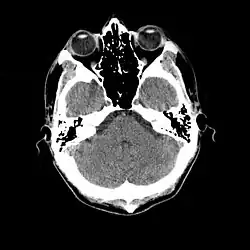

Tomografia computadorizada (português brasileiro) ou tomografia computorizada (português europeu) (TC), originalmente apelidada tomografia axial computadorizada / computorizada (TAC) - em inglês: X-ray computed tomography - é um exame complementar de diagnóstico por imagem, que consiste numa imagem que representa uma secção ou "fatia" do corpo. É obtida através do processamento por computador de informação recolhida após expor o corpo a uma sucessão de raios X. Seu método principal é estudar a atenuação de um feixe de raios X durante seu trajeto através de um segmento do corpo, no entanto, ela se distingue da radiologia convencional por diversos elementos.[1]

A TC baseia-se nos mesmos princípios que a tomografia convencional, segundo os quais tecidos com diferentes composições absorvem a radiação X de forma diferente. Ao serem atravessados por raios X, tecidos mais densos (como o fígado) ou com elementos mais pesados (como o cálcio presente nos ossos), absorvem mais radiação que tecidos menos densos (como o pulmão, que está cheio de ar).[1][3]

Assim, uma TC indica a quantidade de radiação absorvida por cada parte do corpo analisada (radiodensidade), e traduz essas variações numa escala de cinzentos, produzindo uma imagem. Cada pixel da imagem corresponde à média da absorção dos tecidos nessa zona, expresso em unidades de Hounsfield, em homenagem ao criador da primeira máquina de TC.

As imagens tomográficas podem ser obtidas em dois planos básicos: o plano axial (perpendicular ao maior eixo do corpo) e o plano coronal (paralelo a sutura coronal do crânio ou seja é uma visão frontal). Após obtidas as imagens, recursos computacionais podem permitir reconstruções no plano sagital (paralelo a sutura sagital do crânio) ou reconstruções tridimensionais.